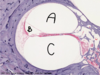

Posterior pituitary stores and releases oxytocin and ADH. THey are synth in hypothal and tranported to post pit.

This is why the post pit consists of (1) unmyleinated axons of neurons that store these hormones. THe storage ends are called herring bodies.

stars: unmyelinated axons that are storing hormones.

A: Pituicytes - plump cells

B: Sinuisoidal capillaries

C: Herring bodies = the terminal bodies of axons where hormones are stored.